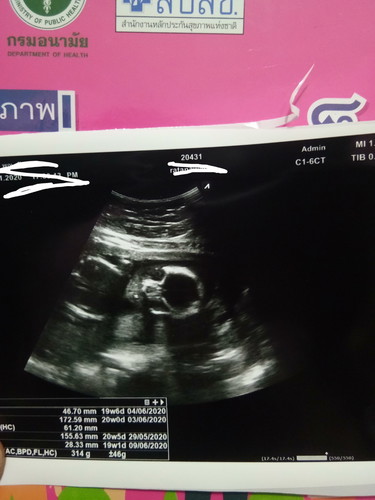

มีใครดูออกมั้ยคะว่าส่วนไหนพอดีเราดูไม่ออกหมอก็ไม่ค่อยแนะนำให้เลยค่ะ

อันนี้หน้าจะเป็นส่วนหัวและใบหน้านะคะ

กี่วีคแล้วคะ ยังดูไม่ออกเลย

20 สัปดาร์แช้วค่ะ